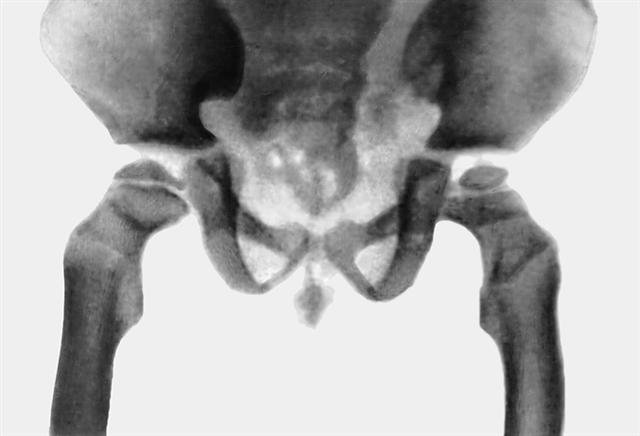

Рис. 2б). Рентгенологические признаки синдрома Гурлер — деформация таза и бедренных костей.